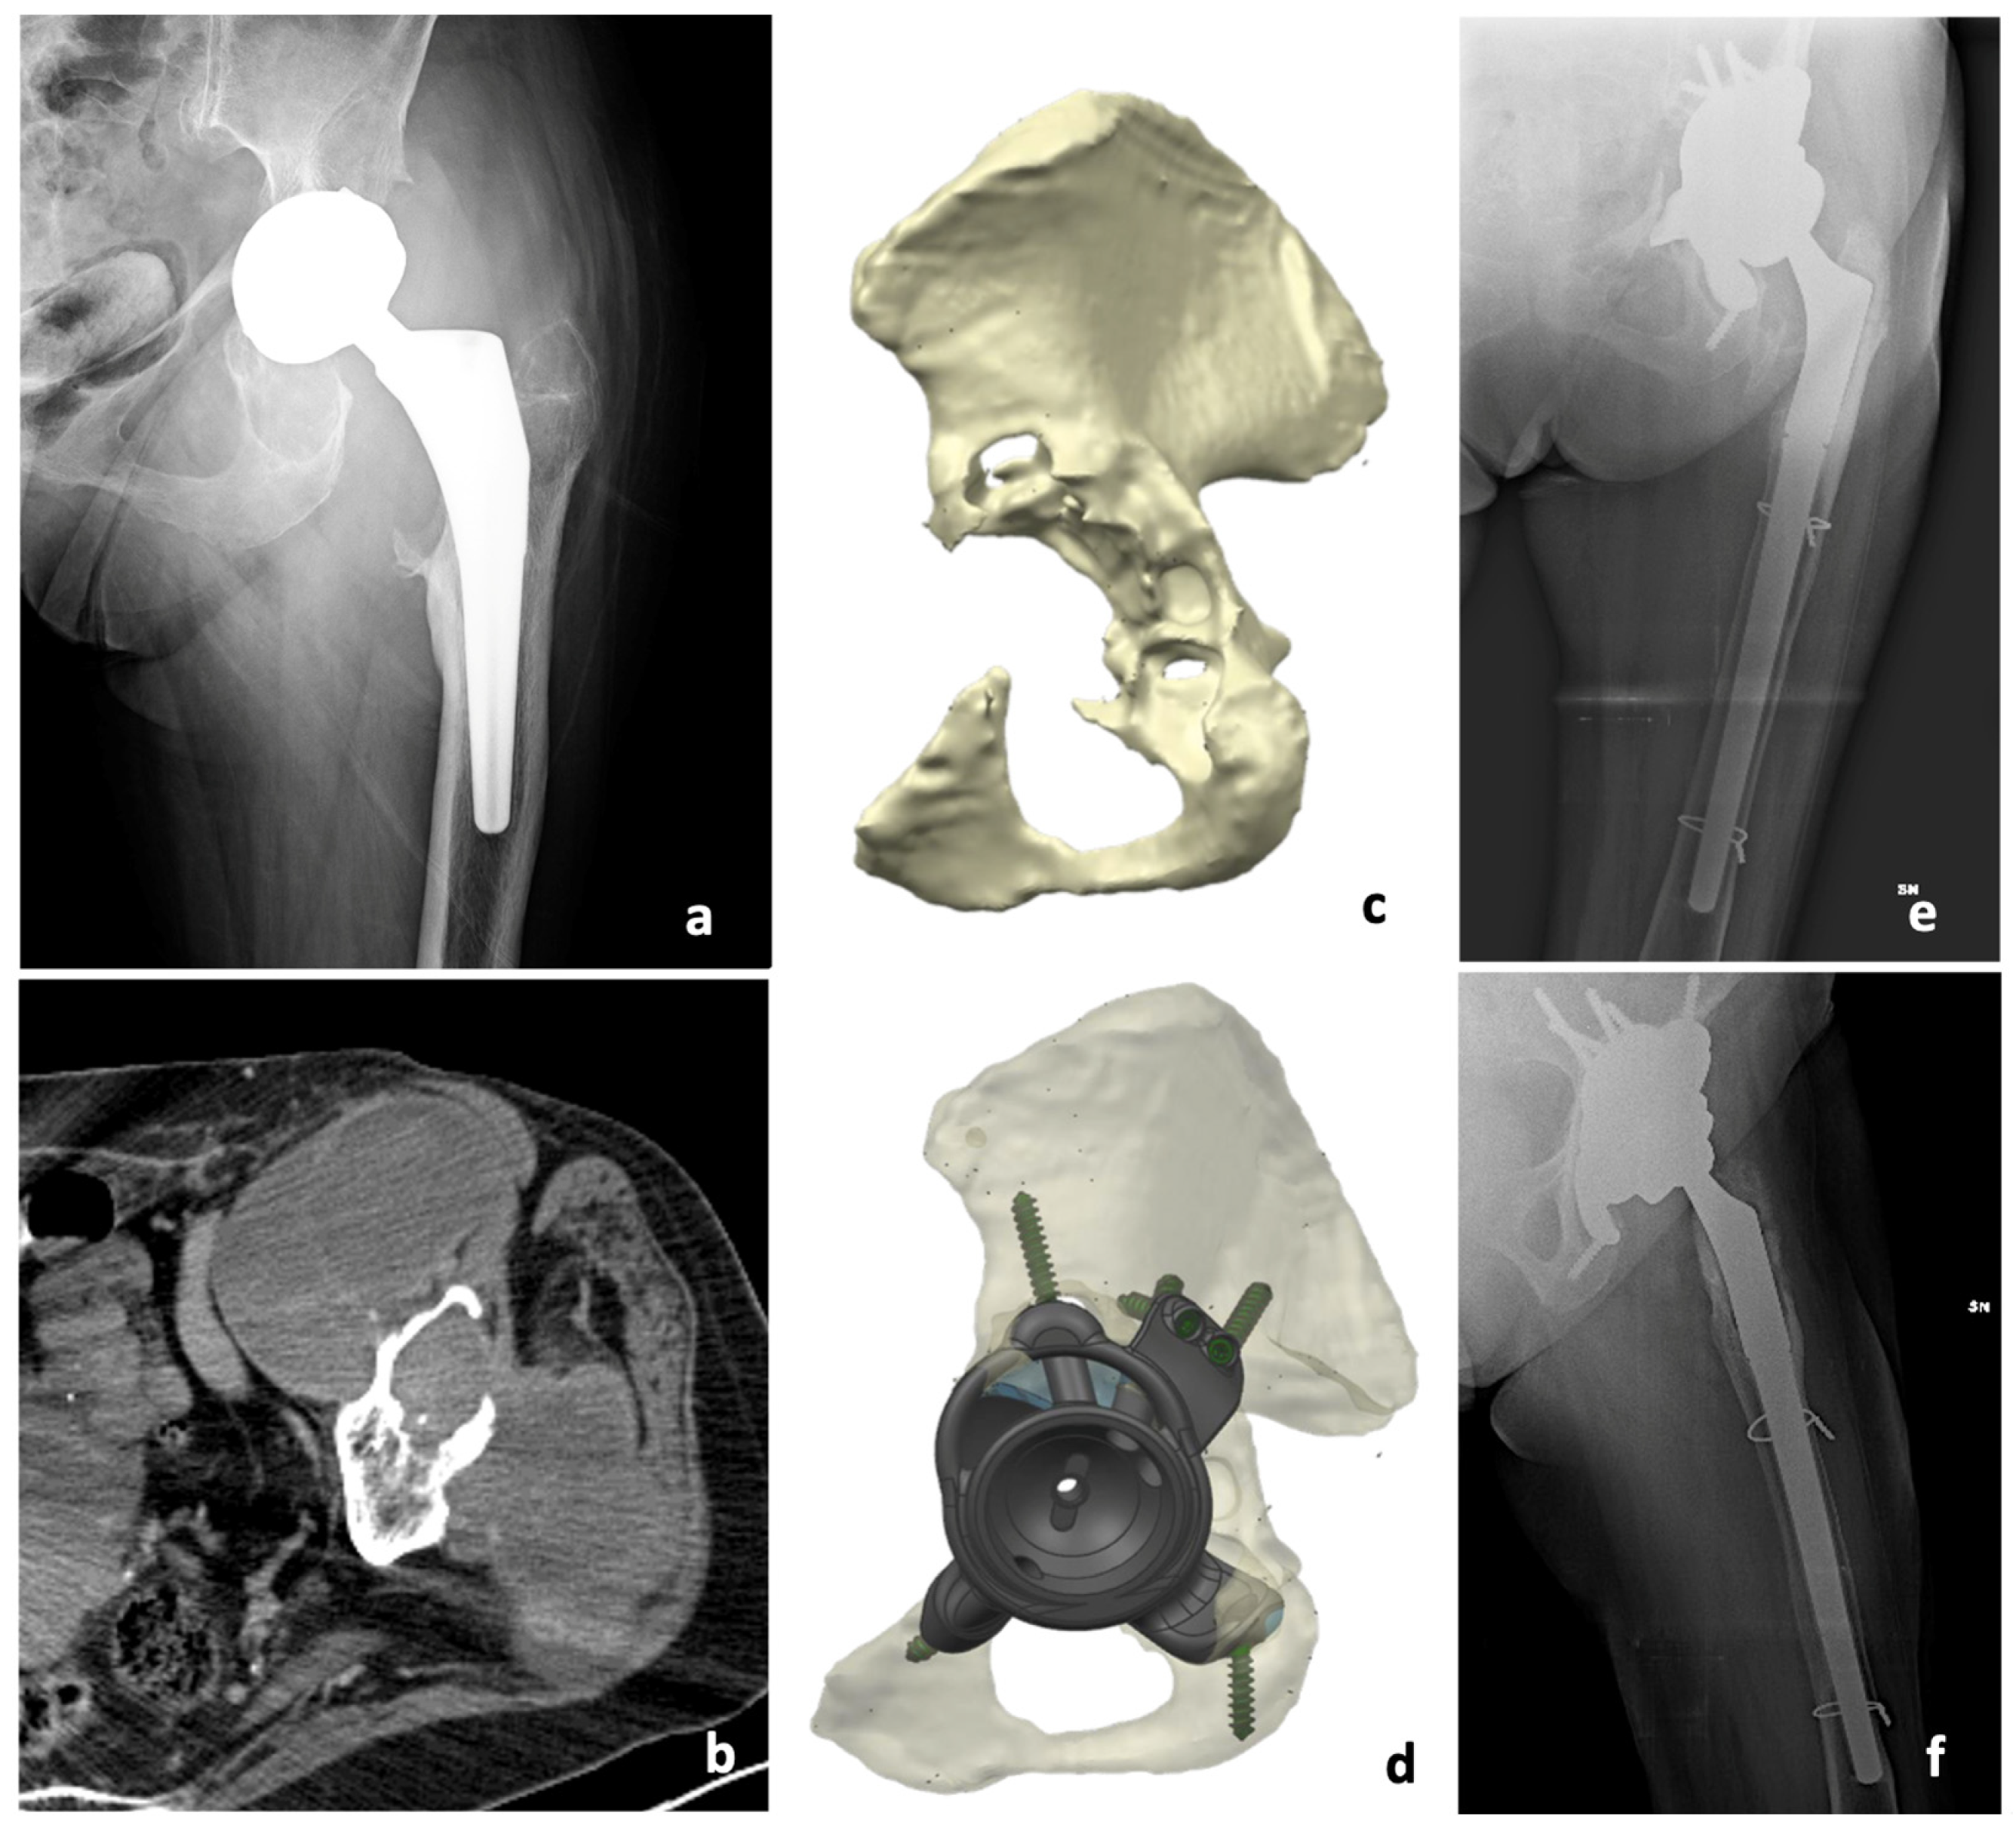

In our study, in 6 cases, we used a standard revision prosthesis, with total hip prostheses in 4 cases and only the acetabular component in 2 cases. In 7 cases, we used a custom-made prosthesis because of bone loss (Figure 1 and Figure S1). We aimed to investigate if there were differences in terms of complications and functional results between the types of surgery.

Figure 1.

Imaging studies and surgical steps from a patient with pseudotumor of the hip treated with a two-stage procedure using an acetabulum custom made 3D printed. Preoperative X-ray (a) and CT scan (b) showing pseudotumor, as well as 3D CT scan performed after the first surgery (c) and 3D-printed model of the acetabular (d) with postoperative X-rays (e,f).